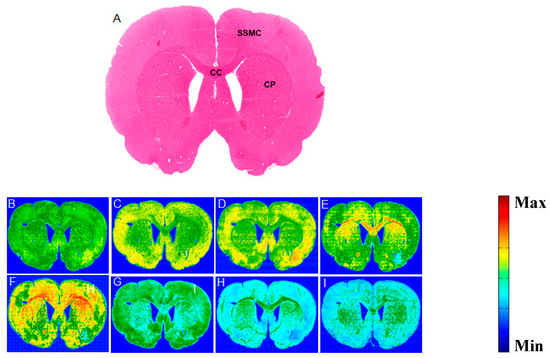

The formalin-fixed paraffin-embedded brain tissue samples (serial sections of 10 μm thickness), were collected from each rat for the FTIR, LA-ICP-MS, and the H&E analyses. The numerical comparisons of the lipid/protein ratio and the ratios of some specific lipid spectral of the regions of interest of this study, are listed in Table 1. Figure 1A shows a rostral section (Bregma 1.56), highlighting three other regions of interest—SSMC, CC, and CP; the corresponding FTIR image is shown in Figure 1B. Figure 1C–I shows the images of the biochemical components—Amide I, Amide II, νas(CH3) asymmetric, νs(CH2) symmetric, νas(CH2) asymmetric stretching, olefin, and ester, respectively. These images were colored, according to the calculated biochemical content values, where red color corresponded to the highest bio-content and the blue color corresponded to the lowest bio-content, as shown on the color bars in the figure. The FTIR spectra of the SSMS, CC, and CP are shown in Figure 2A–C, respectively. Figure 2A represents the SSMC average FTIR spectrum. The spectrum revealed the ester absorption band that arose at ~1730 cm−1 from the ν(C=O) ester (carbonyl) group, had weak absorption. The FTIR spectrum revealed that a robust olefinic=CH band arose at about 3012 cm−1. This was interpreted as that the SSMC structure contains lipids with a high degree of unsaturation. The protein absorption bands, such as amide II, amide I, and the N–H bands, arose at 1545, 1653, and 3290 cm−1, respectively. The amide I and amide II have strong absorption.

Figure 1. (A) H&E staining section of the rostral brain (Bregma 1.56 mm) showing the three regions of interest (ROI): SSMC, CC, and CP. (B) Corresponding FTIR image. (CI) Representative images of the biochemical components—Amide I, Amide II, CH3 asymmetric, CH2 symmetric, CH2 asymmetric, Olefin, and Ester, accordingly. The color bar represents a high concentration, in red, and low concentration, in blue.